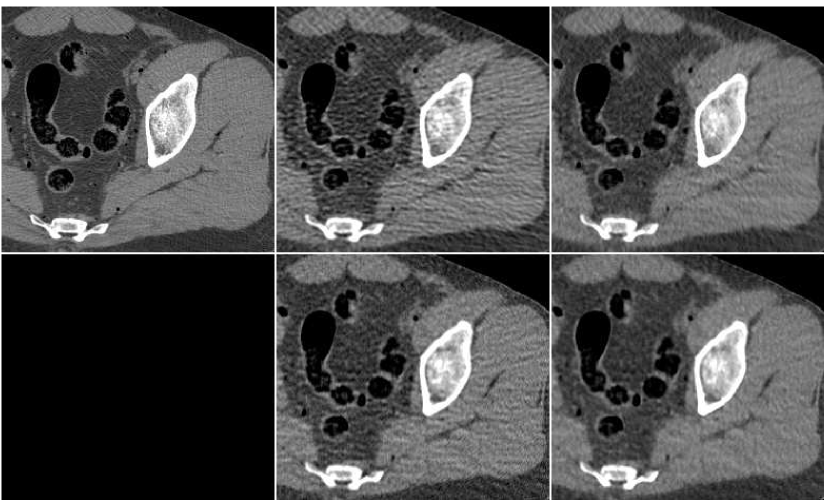

To summarize the fusion effect on the outcome of standard reconstruction algorithms, we display in Figure 12 images produced by both FBP and PWLS methods, before and after applying the proposed method of the ANN-based fusion; these images were previously given in Figures 6,10.

In order to test the robustness of the training results, we apply the ANN trained with the thigh sections, for a reconstruction of images of other body parts – sections of the head and the abdomen. Reconstruction results are presented in Figure 13 in the same order as in the previous comparison: middle image in the upper row is the result of fusion, which components are presented in the lower row. The head reconstruction is improved substantially by the fusion process, as visual observation shows. However, the SNR values (given in Table II) point to the favor of the PWLS image corresponding to iterations (lower middle image). The highest SSIM value does belong to the fusion result, though. In the case of the abdomen section, the fusion image is similar to the -iterations version but contains less noise; its quantitative measures are somewhat better than those of the individual PWLS images.